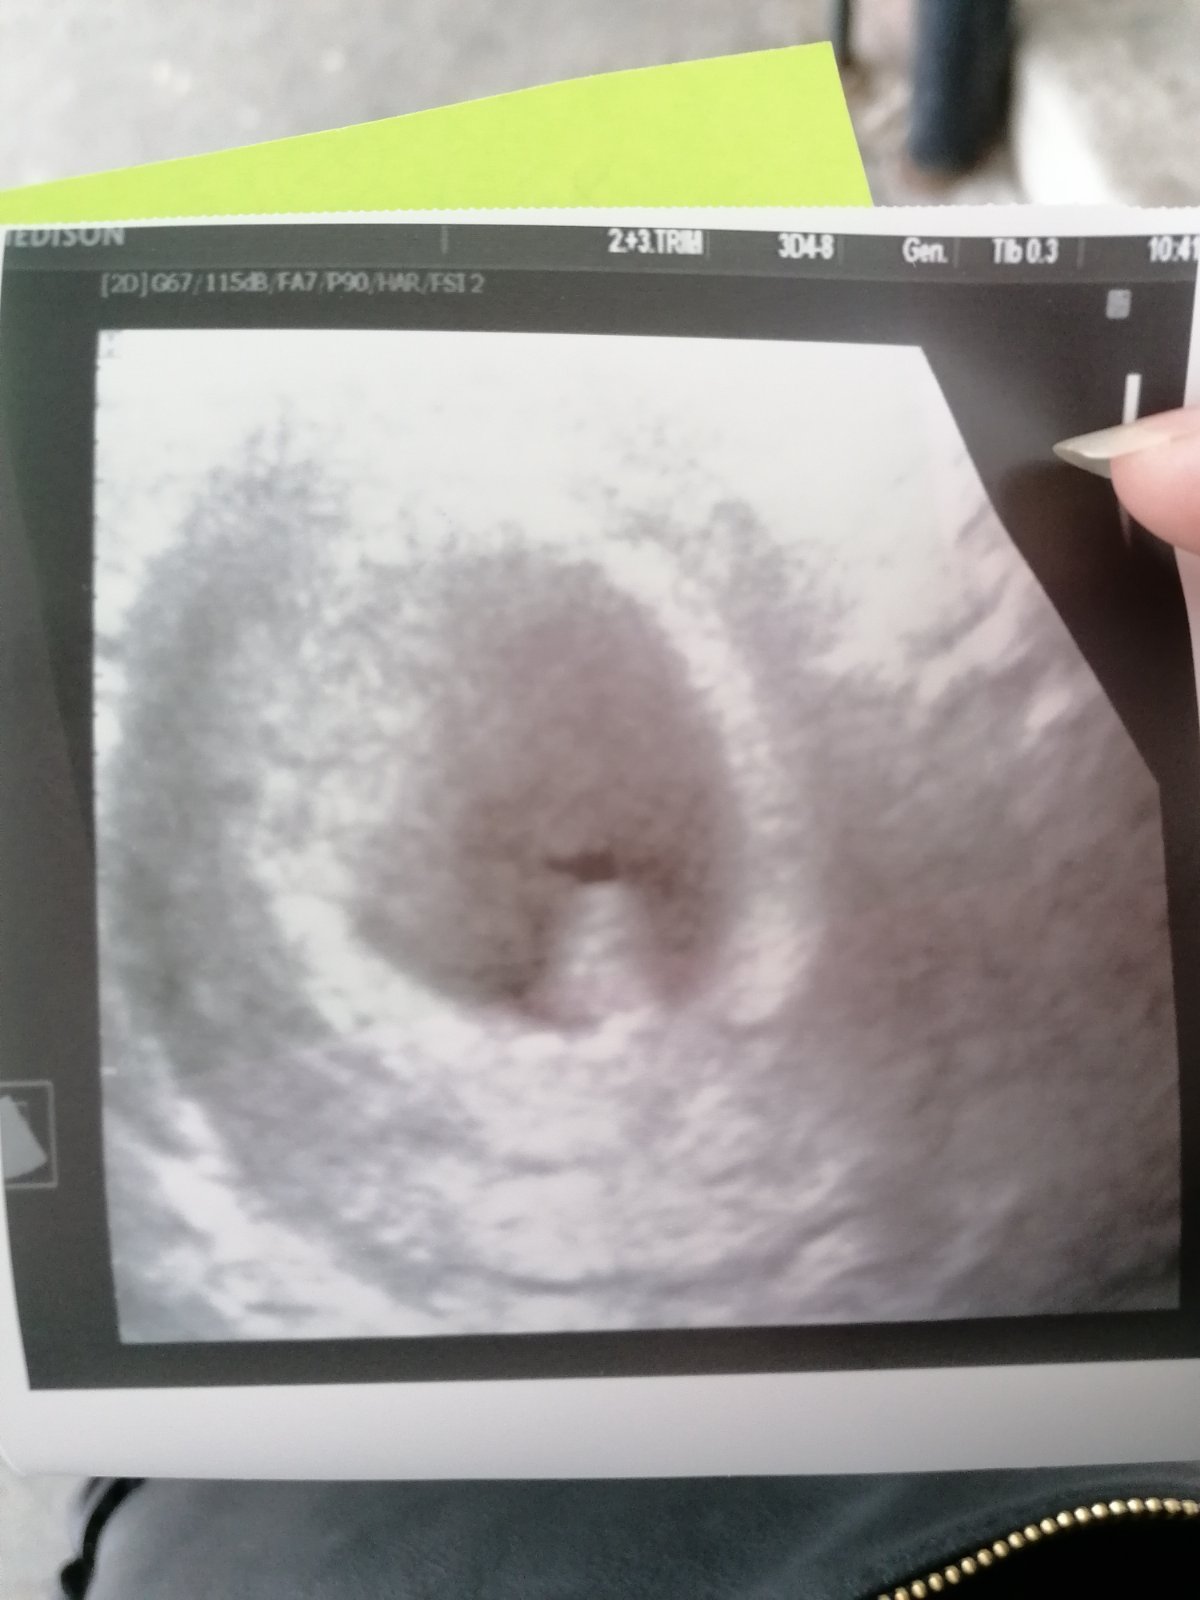

Damy,vraciam sa k Vam 😟 O babo som prisla v 8 tt nebilo mu srdiecko,tak som prezila spontanny potrat,este stale sa cistim,dufam ze ostanem bez kyretu aby sme co najskor boli opat pozehnany babatkom ❤️